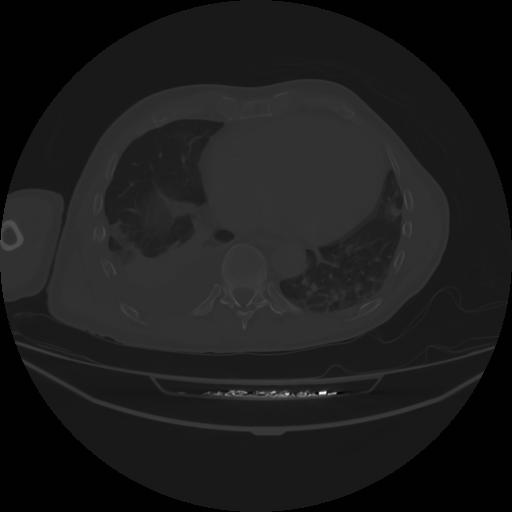

4 CUERPO,CE,Axial,3.0,CUERPO,,